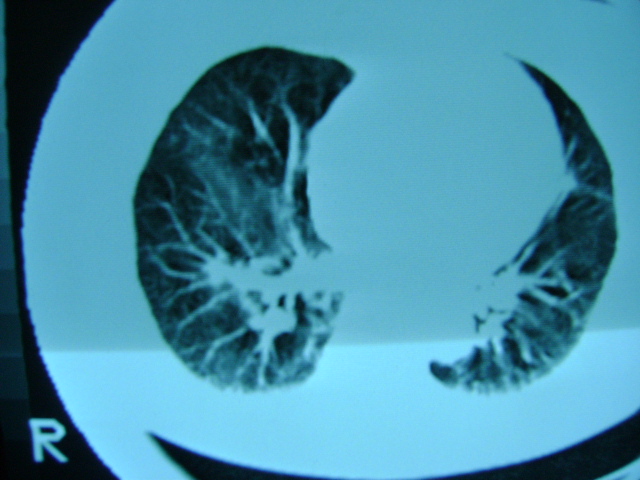

朋友的母亲,56y,咳嗽三个月,感觉左肺门不对,请大家给点意见

左肺门未见异常‘右肺有少许感染,图象质量不好